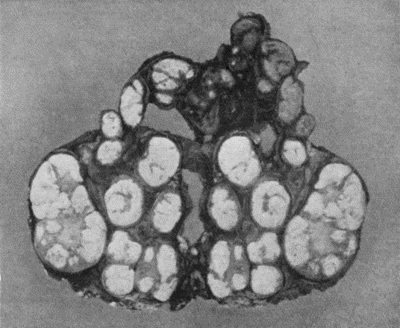

59.Dermoid Cyst of Ovary 213

149.Central Sarcoma of Femur invading Knee Joint 495